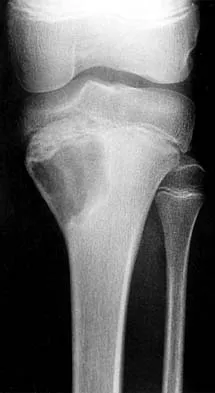

Figure 38 shows the radiograph of a 16-year-old wrestler who injured his elbow when he was thrown to the mat by his opponent. To minimize additional trauma to the medial soft tissues, the elbow should be reduced in

Explanation